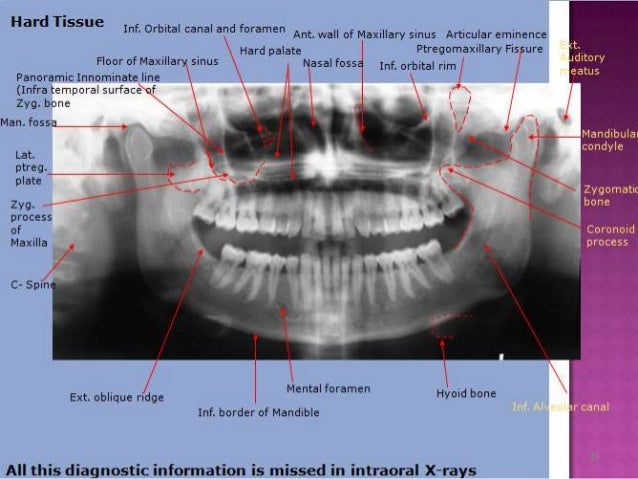

Anatomical Landmarks In Periapical And Orthopantomogram X-ray

Anatomical landmarks in Periapical and Orthopantomogram X-ray www.slideshare.net

orthopantomogram periapical opg orthopantomography xray radiographic anatomic appearance

Septum nasal anatomy hematoma septal bone rhinitis chronic. Orthopantomogram periapical opg orthopantomography xray radiographic anatomic appearance. Nasal septum cavity